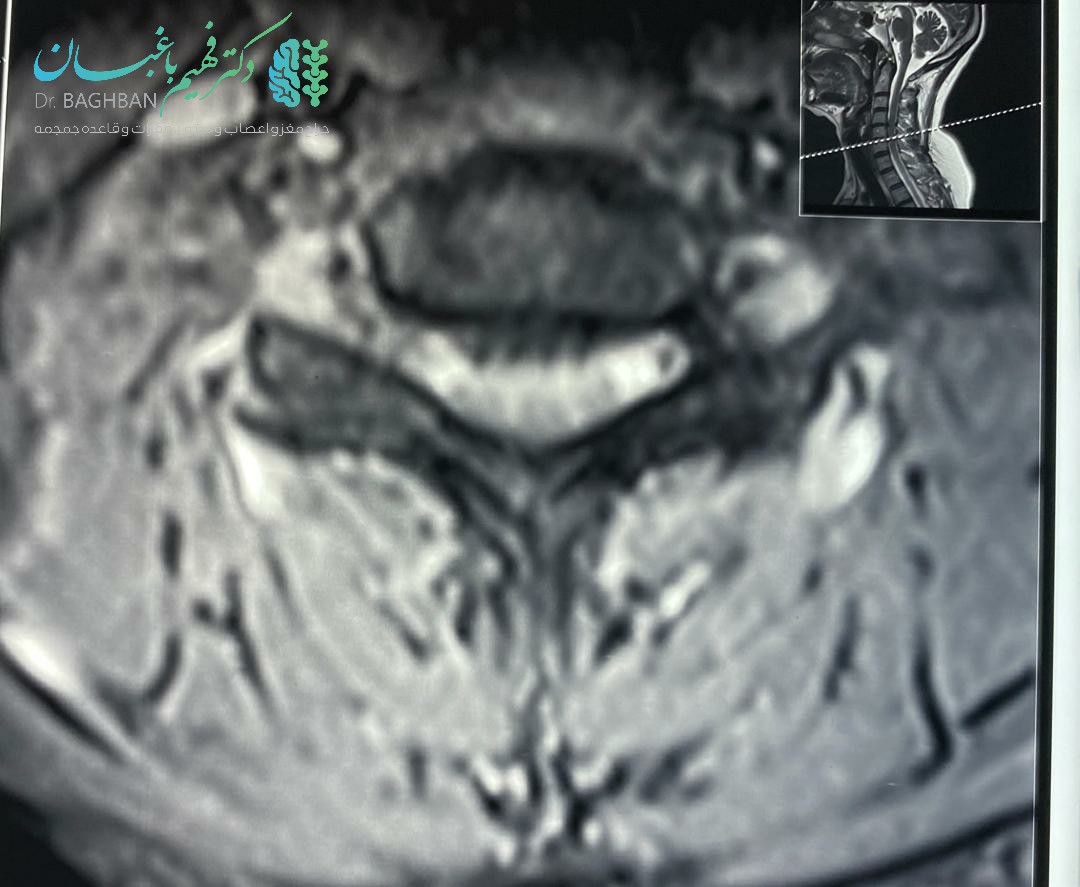

تصاویر قبل از عمل

قبل از عمل دیسک گردن

قبل از عمل